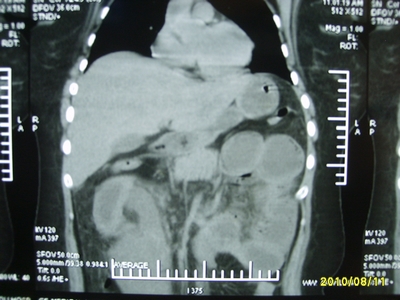

5天前突发腹痛剧烈难忍,伴解淡血水样便。近一天来腹痛缓解,没有明显的腹膜炎的体征。今天照的腹部ct。从ct上看感觉是一个绞窄性肠梗阻,但是现在没有腹痛。不好解释

要有麻烦了,感觉小肠有套叠还有扭转改变,估计部分已有坏死。

高位肠梗阻(不全性),原因小肠(空肠)扭转,肠壁水肿增厚,成年人肠梗阻要排除合并占位,建议手术。

绞窄性肠梗阻_肠管套叠 扭转,肠壁明显水肿。

病人现在没有腹痛。怪了。从影像上来看。确实是绞窄了。但是没有腹痛。没有明显的腹膜炎的体征。确实有不好解释。难道是坏死了。反而不痛了。怪怪怪

支持绞窄性肠梗阻,肠壁明显水肿并见有多发小泡状积气--肠坏死

考虑绞窄性肠梗阻并肠坏死。

考虑绞窄性肠梗阻并肠坏死,手术吧